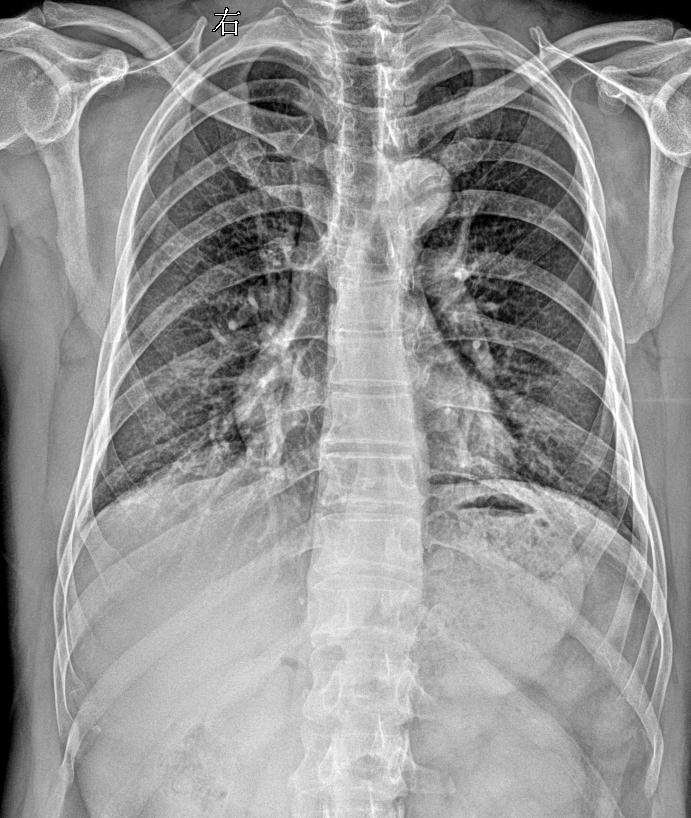

男 45外伤 胸廓正斜位

2025-11-09 19:06